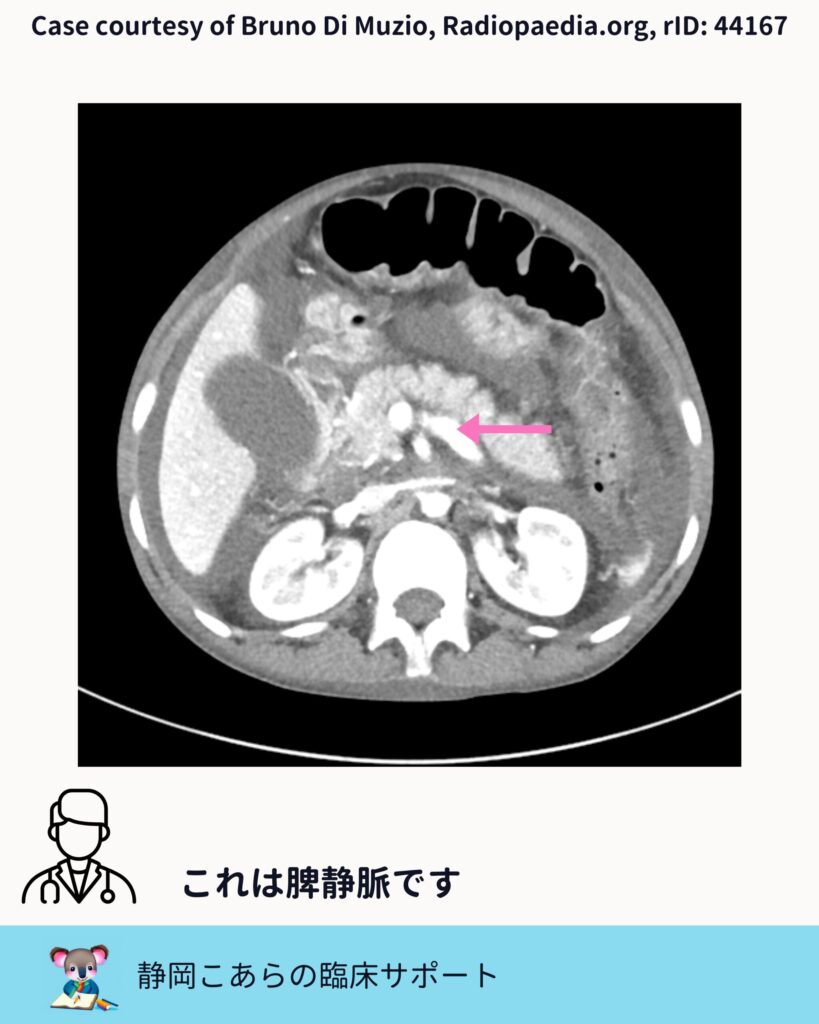

脾静脈との合流

次に確認するのが脾静脈です。膵の背側を水平に走る太めの静脈で、これもCTでは比較的見つけやすい構造です。

上腸間膜静脈と脾静脈。この二つが合流したところが、門脈になります。